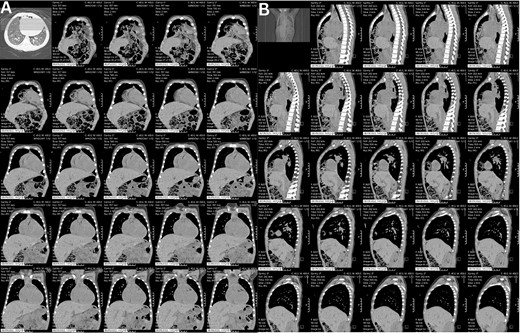

A preoperative assessment revealed an unexpected diaphragmatic hernia found incidentally on a routine chest X-ray (Fig. 1). This led to further tests, including a chest computed tomography (CT), which showed a central diaphragmatic defect with part of the transverse colon herniated into the chest (Fig. 2). Additionally, echocardiography found a perimembranous VSD with bidirectional shunting and mild tricuspid valve regurgitation. Cardiac catheterization confirmed reactive pulmonary vascular resistance.

This is a preoperative chest X-ray with an AP view revealing subtle lucent mediastinal structures in the lower mid-chest.

These CT chest scans in the coronal (A) and sagittal (B) planes, showing an anterior central diaphragmatic defect measuring 4.3 cm × 2.8 cm (TR × AP) with intrathoracic herniation of part of the transverse colon.